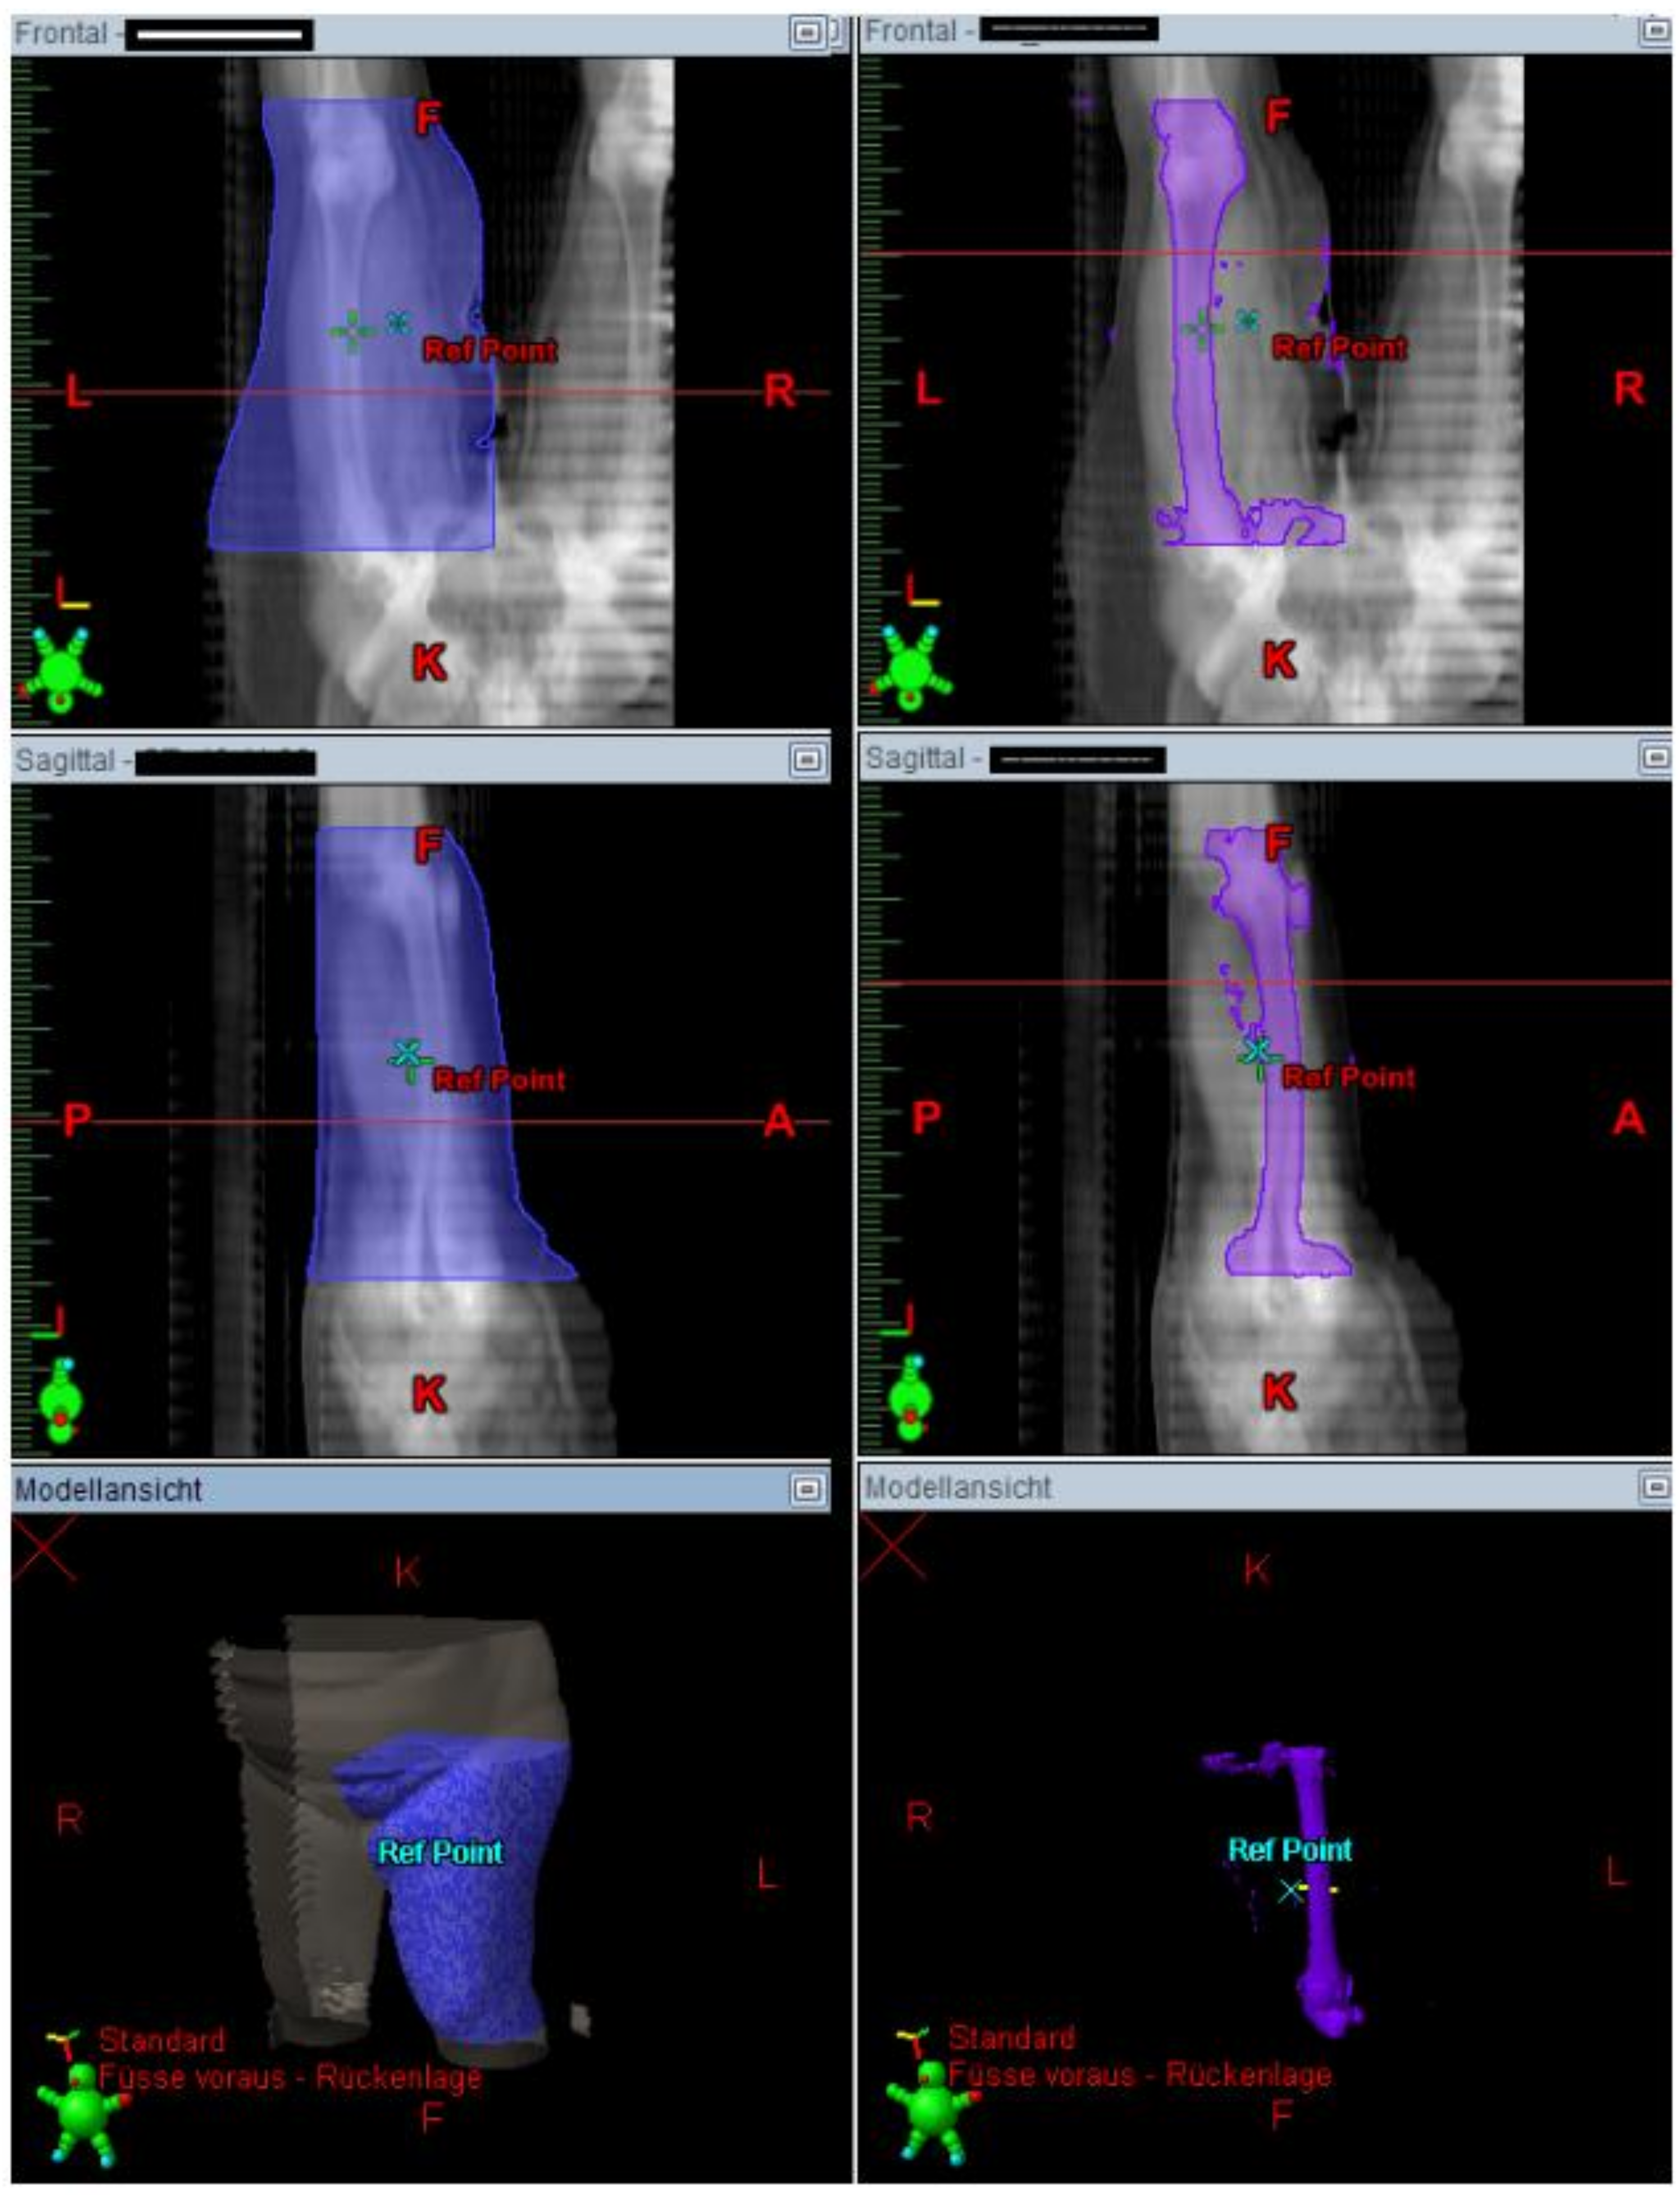

The Lymph-Sparing Quotient

Use of the Lymph-Sparing Quotient